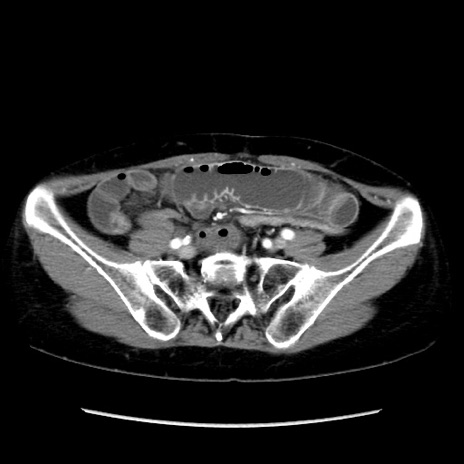

症例32(横断像)

【症例】40歳代 女性

【主訴】上腹部痛、嘔気・嘔吐

【現病歴】約9時間前頃から急に上腹部痛、嘔気、嘔吐が出現。改善しないため救急要請。

【既往歴】子宮頚癌(広汎子宮全摘術、放射線療法)、腸閉塞

【身体所見】腹部:平坦、軟、腸雑音亢進、上腹部を中心に腹部全体に圧痛あり。

【データ】WBC 8400、CRP 0.03